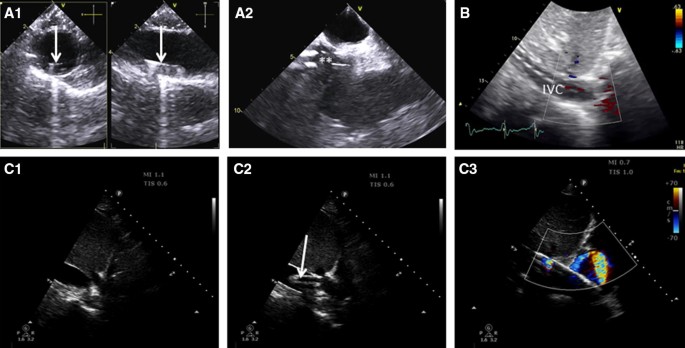

Handheld Echocardiography For Critical Care. Transthoracic TTE and transesophageal TEE echocardiography are important investigations for many patients in the intensive care unit ICU to diagnose acute cardiac pathologies and assess the haemodynamic status 1. HHE can help assess chamber size ventricular function and presence of fluid collections and thus is useful in determining etiology of shock and measuring volume status. Hand-held echocardiography HHE is being explored for use in the intensive care arena as an extension of the physical examination for real time and iterative information. It allows the intensivist to categorize shock state and to determine the appropriateness of rapid volume resuscitation.

Basic advanced and expert. Critical care echocardiography CCE is performed and interpreted by the intensivist at the bedside to help in the diagnostic work-up and to guide therapy for patients with acute circulatory and respiratory failure. Handheld or hand-carried ultrasound HCU devices are small light battery powered less expensive systems with good 2D imaging quality and full Doppler capabilities often with digital and wireless communication some with stress and TEE options. Transthoracic TTE and transesophageal TEE echocardiography are important investigations for many patients in the intensive care unit ICU to diagnose acute cardiac pathologies and assess the haemodynamic status 1. Echocardiography is a powerful diagnostic and monitoring tool of cardiac performance cardiac pathology and extracardiac intrathoracic abnormalities. This is followed by a review of Doppler principles including pulsed wave continuous wave and color flow Doppler.